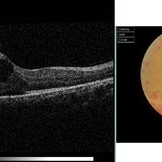

Best Disease Best DiseaseMar 9 2013 by Hamid Ahmadieh, MD OCT of the right eye of a 49-year-old man with decreased VA due to advanced Best disease. Photographer: Soodabeh Fooladin, Negah Eye Center, Tehran Imaging device: Heidelberg Spectralis Condition/keywords: Best disease, optical coherence tomography (OCT)